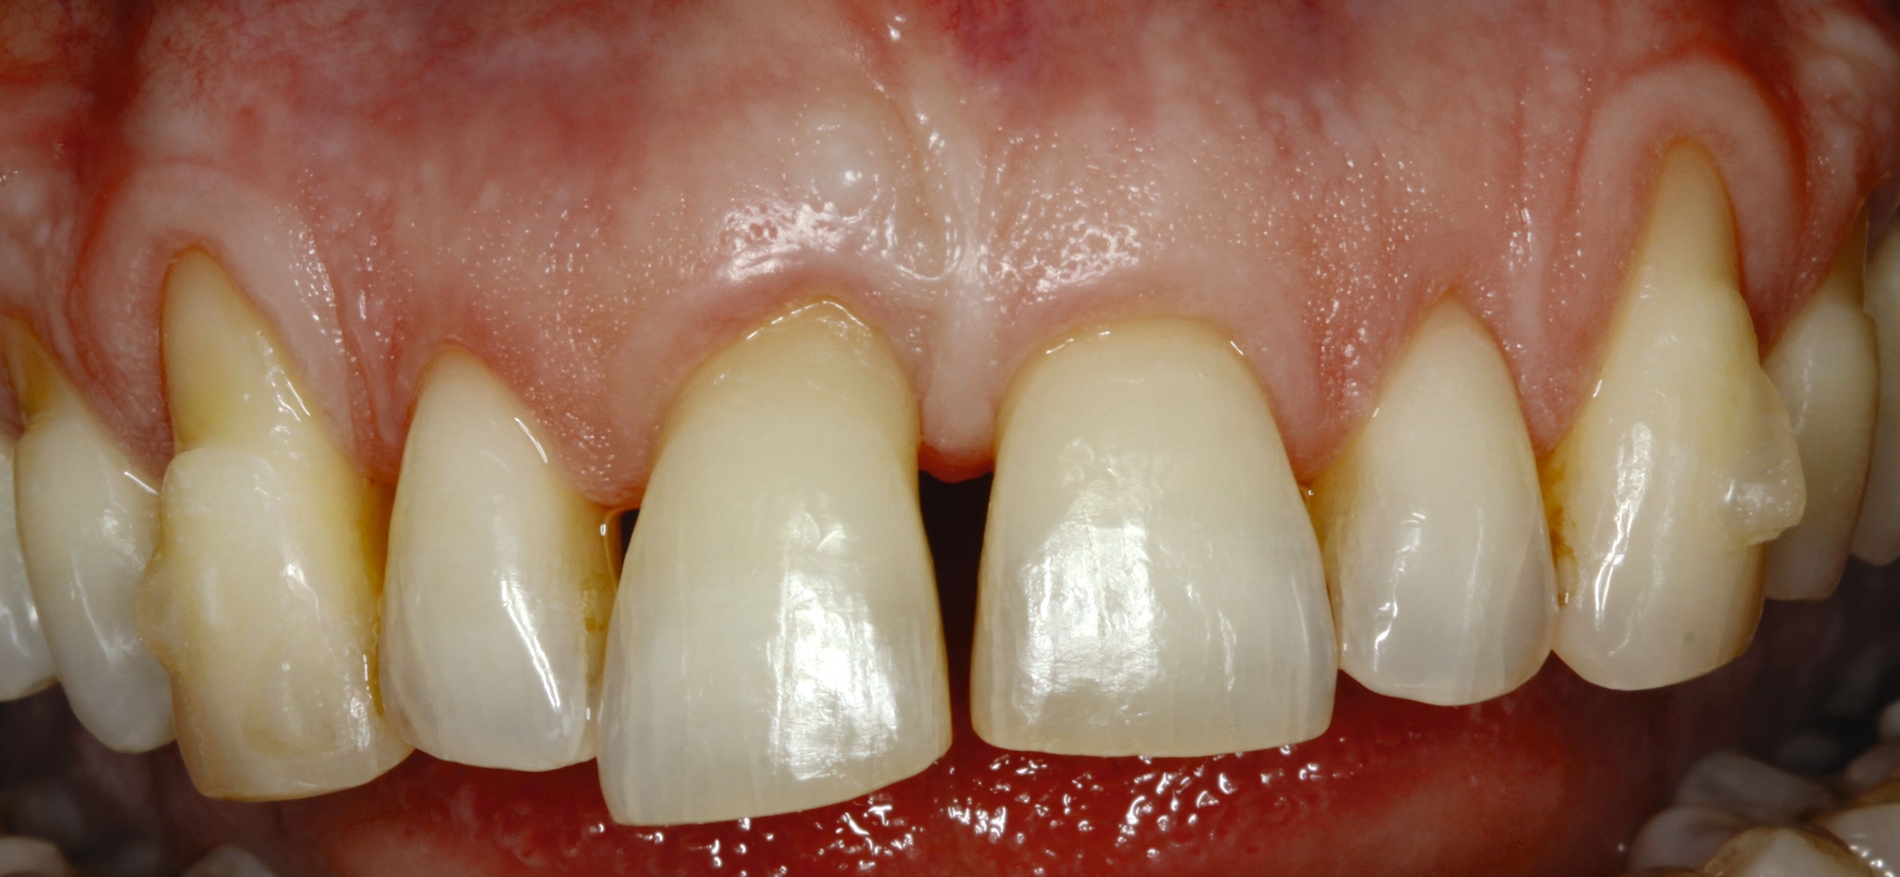

Möglichkeiten zur Therapie des okklusalen Traumas sind das selektive Einschleifen okklusaler Frühkontakte, die Schienung der betroffenen Zähne oder gegebenenfalls auch kieferorthopädische Bewegungen der Zähne sowie eine Kombination der genannten Therapieformen [Fan und Caton, 2018; Dommisch et al., 2022]. Ein Beispiel für eine Schienung bei Vorliegen einer okklusalen Dysfunktion ist in Abbildung 2 dargestellt.

Es gibt viele Möglichkeiten, permanente Schienungen von Zähnen mit Komposit alleine oder in Kombination mit Glasfasern durchzuführen. Die Verblockung der Approximalräume benachbarter karies- und füllungsfreier Zähne mit Komposit stellt eine ästhetisch akzeptable Schienung dar und kann so vorgenommen werden, dass die parodontale Reinigungsfähigkeit erhalten bleibt (Abbildung 5). Als Nachteil dieser rigiden Schienungsform sind mögliche Schienungsfrakturen zu nennen, die insbesondere bei höheren Mobilitätsgraden vorkommen. Glasfaser-Komposit-Schienungen weisen ebenfalls eine hohe Rigidität auf. Sie können zahnhartsubstanzschonend an den oralen Flächen der Zähne angebracht werden. Alternativ kann bei gut ausgeformten Zahnbögen im Frontzahngebiet eine inzisale Schienung vorgenommen werden. Dafür ist zumeist eine Präparation erforderlich, um Platz für das Schienungsmaterial zu schaffen. Bei approximalen Füllungen oder bei Karies an angrenzenden Flächen benachbarter Zähne können auch zwei Approximalfüllungen miteinander verbunden werden, um eine Schienung durchzuführen.

Eine weitere Möglichkeit der permanenten Schienung besteht in der vertikalen Verlängerung des Kontaktpunktes von Zähnen durch hochwertiges Kompositmaterial im Rahmen von Frontzahnverbreiterungen zur Reduktion der „schwarzen Dreiecke“ (Abbildung 6). Diese Schienungsform erhält die physiologische Eigenbeweglichkeit der Zähne und die parodontale Reinigungsfähigkeit.